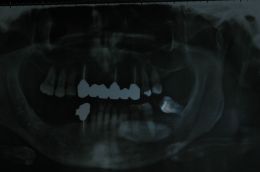

Sottoponiamo il paziente ad accertamenti diagnostici di tipo radiologico, sottoponendolo a ortopantomografia delle arcate dentarie ( Foto 2) da cui si intravede una formazione radiopaca di forma ovalare nella regione mandibolare destra, all’ingrandimento (Foto 3) si rileva la continuità dei bordi. Essendo l’O.P.T. una RX bidimensionale sottoponiamo il paziente ad una RX occlusale da cui rileviamo che la formazione è dispersa nei tessuti molli del pavimento linguale. ( Foto 4)